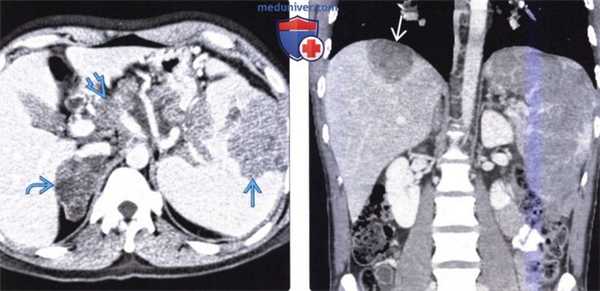

(Слева) На аксиальной КТ с контрастным усилением у пациента с неходжкинской лимфомой определяется выраженное увеличение селезенки с наличием опухолевых очагов с неоднородной структурой, слабо накапливающих контраст. Обратите внимание на лимфоидную инфильтрацию надпочечника и диффузное поражение внутрибрюшных лимфоузлов.

(Справа) На корональной КТ с контрастным усилением у пациента с меланомой визуализируются множественные метастазы, практически полностью замещающие нормальную ткань селезенки, а также метастаз в паренхиме печени под диафрагмой.